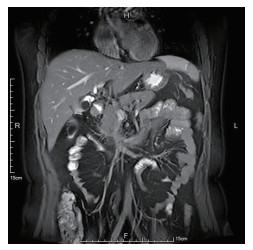

术中怀疑患者存在双胆囊管胆道畸形,用电凝钩将其中较为纤细的管腔沿横轴方向切一小口,见金黄色胆汁溢出,用直角分离钳前端顺此管腔向远端探行可进入胆总管。电凝切开另一支较粗管腔,同样见有胆汁溢出后,用胆道镜深入管腔,向胆总管方向伸入,可见左右肝管开口,胆囊管汇入处距离左右肝管开口较近,符合术前上腹部MRCP表现(图 3)。

图  3   术前上腹部MRCP冠状位影像

胆囊管汇入胆总管位置较高,距离左右肝管开口较近.MRCP:磁共振胰胆管造影.